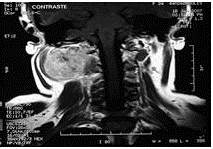

Se trató de paciente femenina de 25 años de edad quien inició enfermedad actual en el año 2007, presentando aumento de volumen y dolor de leve intensidad en región de la nuca. Paciente asintomática con tumor palpable de aproximadamente 10 cm x 10 cm, en base del cráneo extendiéndose a región latero-cervical derecha (Figura. 1).

or este motivo se le realizó estudios imaginológicos como resonancia magnética nuclear (RMN) identificándose lesión ocupante de espacio (LOE) de bordes regulares que mide 10 cm x 6 cm, ubicado en región cervical profunda posterior y lateral derecha desde la base del cráneo hasta C3, de bordes regulares hiperintensa, con compresión de estructuras vasculonerviosas, pudiendo corresponder a un proceso sarcomatoso, sin descartar otro proceso de tipo neurofibroma (Figura 2).